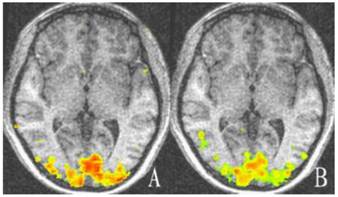

For amblyopic eyes, the activation area of the striate cortex (0.45 ± 0.035) was significantly lower than that of the sound eyes (0.49 ± 0.030, P < 0.05). The activation area of the extrastriate cortex (3.55 ± 0.234) was also significantly lower than that of the fellow eyes (3.77 ± 0.257, P < 0.05; Fig. 1, 3). The cortex activation data are summarized in Table 3. The ID of extrastriate cortex activation had no correlation with that of the striate cortex (R2 = 0.45, P = 0.557), which suggested the striate and ESC deficits are independent and the latter do not arise as a down-stream consequence of the primary visual cortex lesion.

Figure 3

The activation map of the amblyopic and sound eyes relative to baseline for amblyopic children. The activation areas of the amblyopic eyes are much less than that of the sound eyes in striate and extrastriate cortex (P < 0.05). A: Activation map of amblyopic eyes; B: Activation of the sound eyes. Areas with high and low activation are indicated by red and green colors.